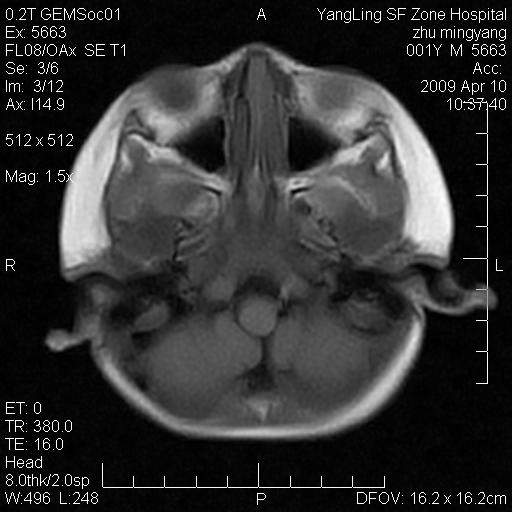

患者:1岁半,两天前外伤收住我院,ct检查小脑占位

考虑星形细胞瘤,建议增强

髓母细胞瘤或血管母细胞瘤,增强后可以鉴别;影像资料见 <。鱼博浪老师的《中枢神经系统ct与mr鉴别诊断》 小脑部肿瘤章节。

髓母细胞瘤或血管母细胞瘤!支持!

支持考虑髓母细胞瘤

考虑----髓母细胞瘤可能性大

考虑髓母细胞瘤或室管膜瘤。

支持髓母细胞瘤。

考虑髓母细胞瘤。

考虑髓母细胞瘤或星形细胞瘤

考虑髓母细胞瘤.

小脑肿瘤.考虑髓母细胞瘤可能.

就病灶部位及临床资料首先考虑髓母.